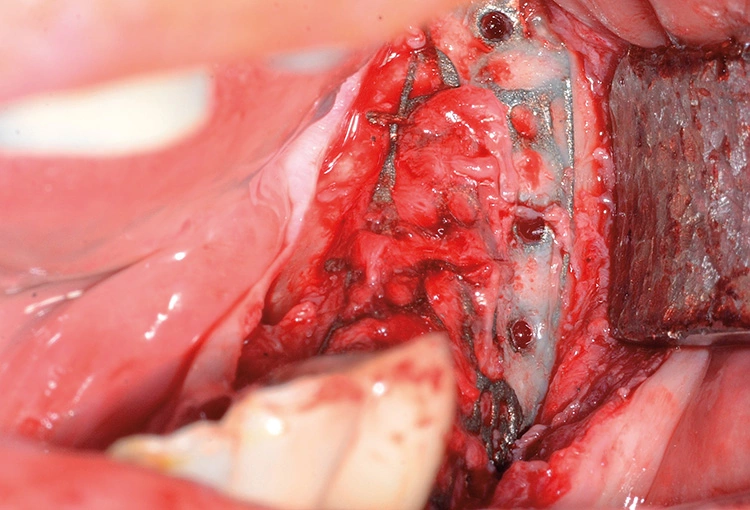

Implantation: 7 Monate nach Augmentation

Tröltzsch

Tröltzsch Tröltzsch

Tröltzsch Tröltzsch

Tröltzsch Tröltzsch

Tröltzsch Tröltzsch

Tröltzsch Tröltzsch

Tröltzsch Tröltzsch

Tröltzsch Tröltzsch

Tröltzsch Tröltzsch

Tröltzsch

Trotz der schlechten, hart- und weichgewebigen Grundvoraussetzungen konnte der Kieferkamm zufriedenstellend rekonstruiert werden. Die Augmentation des kombinierten, horizontalen und vertikalen Defekts mit Yxoss CBR®, Geistlich Bio-Oss®, Geistlich Bio-Gide®, autologem Knochen und PRF ermöglichte die Implantation mit hoher Primärstabilität in den rekonstruierten Bereich.